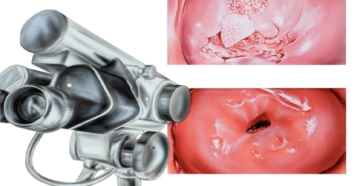

Боль при осмотре зеркалом у гинеколога Дмитрий Лубнин акушер-гинеколог, кандидат медицинских наук Почему возникает боль…